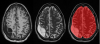

Description:A subject with subdural and subacute epidural hematoma